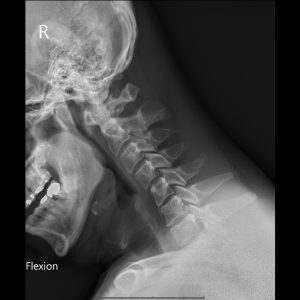

C spine Flexion view